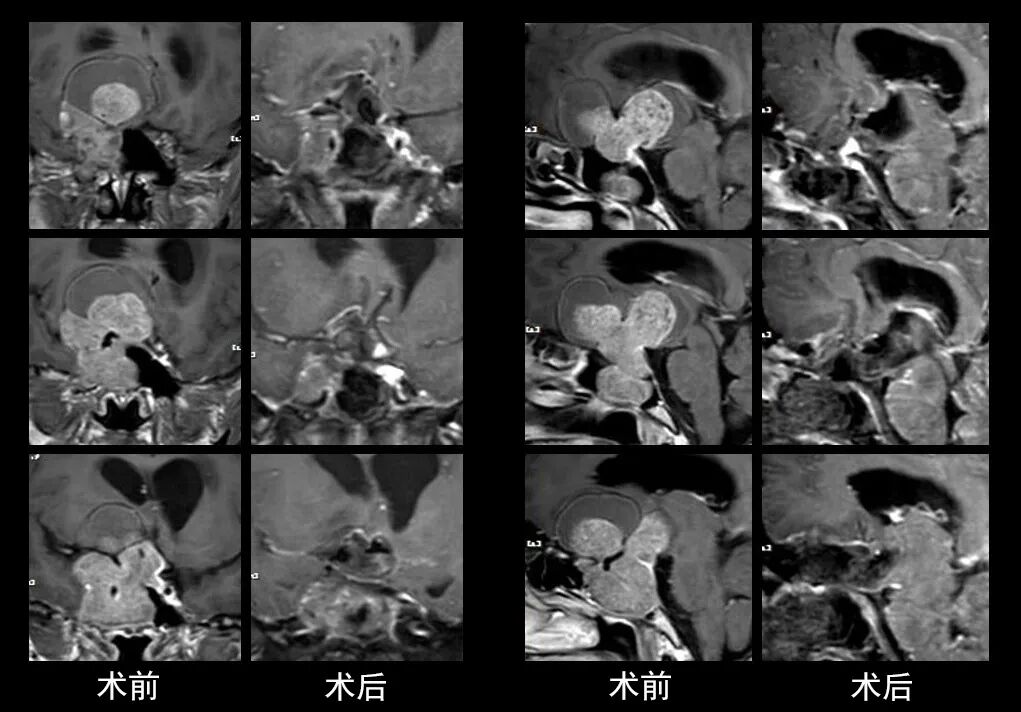

本研究中采用联合手术策略的代表性病例展示:

左右滑动查看更多

图片

case 3

case 4